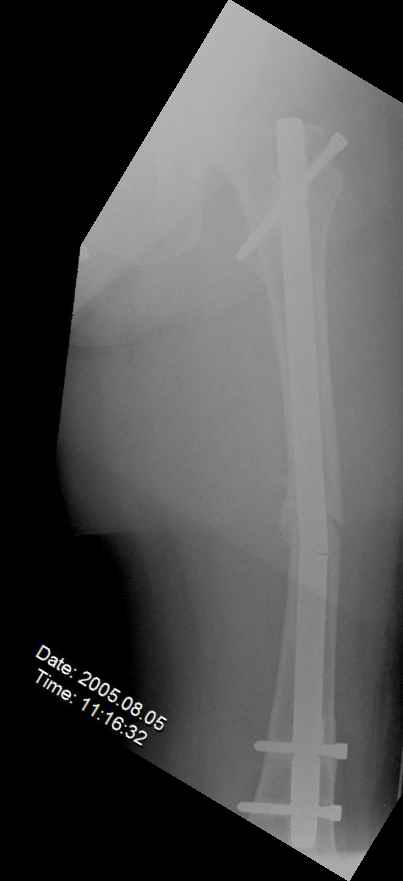

May I have some advice on the following case? Middle aged woman, No chronic medical problems, +tobacco use - but she promises she's going to quit! Original MVC in late 1990's, initial rod failed, and 2 subsequent exchanges failed (most recently shown in attached jpgs.)

Most recent one (6/2002) was apparently an open nailing to remove last broken nail, but no grafting was performed in conjunction. Now sent to me with broken 14mm R/T nail in place.WBC, Hgb, Chemistries normal.ESR 34CRP 4.2No other apparent locus of infection.I was considering a staged approach - removing nail and screws and obtaining cultures.If negative, proceed with exchange nailing with open grafting +/- BMP, But how best to deal with that pedestal distally and avoid anterior breech near patella? If positive cultures, what would be best option?Thanks. Tom Schaller Kalamazoo, MI.

In my opinion, there is no nail strong enough to tolerate a varus deformity of femur after nailing. The AP view of the distal femur shows that the femur has been repeatedly nailed in varus. The tip of the nail is short and lateral in distal lateral metaphysis. It should be central over the intercondylar notch and buried in the distal epiphyseal scar. This has resulted in constant bending forces on the nail (see the "windshield wiper" sign) and its eventual fatigue failure.

I would first determine the degree of varus deformity with a long standing AP x-ray. After nail removal, irrigation, debridement and reaming of the nonunion, specimens would be sent for pathology and culture. If there was any sign of infection, placement of custom made antibiotic nail e.g.

for two or three weeks would be performed before an ORIF plate fixation with Judet decortications and bone graft.

My first definitive treatment choice would be a long lateral tension band plate with insertion of proximal screws directed proximally at an angle of about 25-30 degrees. Correction of the varus would be accomplished by using a tensioning device distally or compressing with two eccentrically placed distal screws simultaneously as shown in Lawrence Webb's OTA BFC lecture

or two distal screws directed distally. Fixation would be completed by a pair of locking screws each side of the nonunion..